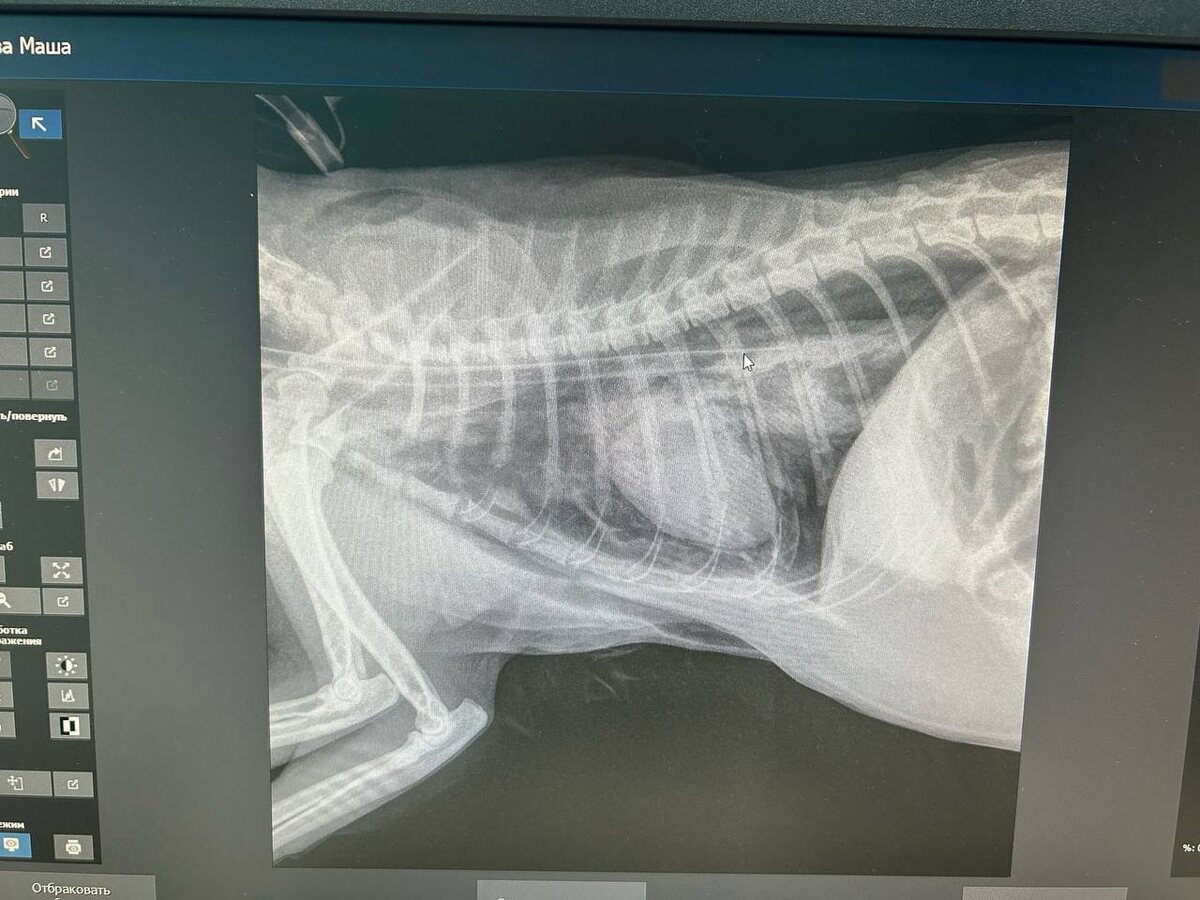

Маша в тяжелейшем состоянии, врачи борются за её жизнь

Маша в тяжелейшем состоянии, врачи борются за её жизнь! Прогноз очень осторожный 😰

Маша в тяжелейшем состоянии, врачи борются за её жизнь!

Прогноз очень осторожный 😰